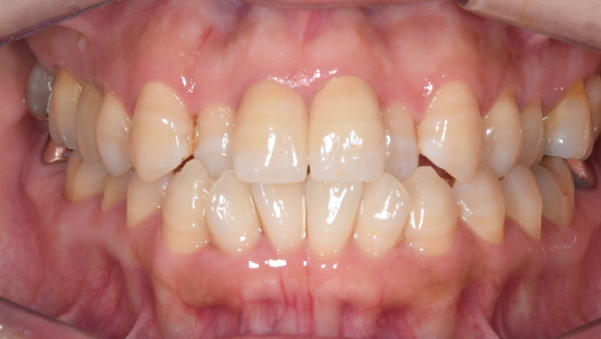

症例写真(治療後)

【担当医師所見】

治療後:

矯正治療と虫歯の治療すべて終わったときの写真になります。見た目も最初の頃とは全く違いますし、お口の中もすごく綺麗です。